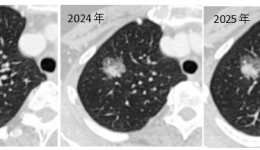

只因忽视医生定期复查的医嘱,小结节差点变成“大问题”!近日,茂名市人民医院胸外科团队在广东省人民医院(以下简称省医)帮扶专家、茂名市人民医院胸外科执行主任张升博士的带领下,成功为一名62岁的“肺浸润性腺癌”女性患者实施单孔胸腔镜下肺...